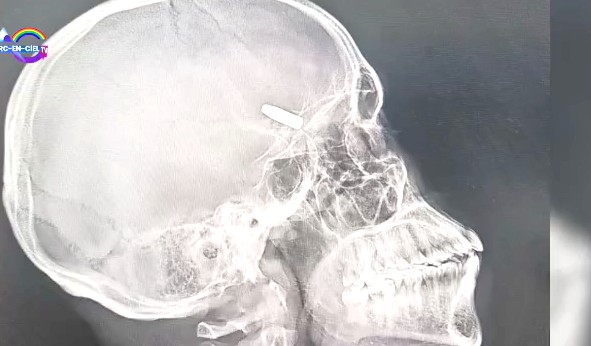

À Lubumbashi, dans la province du Haut-Katanga, une opération chirurgicale d’un genre inédit a récemment été menée avec succès au Centre médical Tshisekedi Tshilombo (CMTT). Une balle a été extraite du crâne d’un patient grâce à une technologie de pointe, la neuronavigation, dans une salle d’opération répondant aux standards internationaux. L’intervention, qui n’a duré qu’une vingtaine de minutes, s’est déroulée sans ouverture préalable du crâne. Trois heures plus tard, le patient était réveillé, lucide, sans aucun déficit neurologique.

L’opération a été conduite par le Dr Dieumerci Kabulo, médecin-directeur du centre, à l’aide de la neuronavigation, une technologie encore inédite en Afrique centrale. « C’est une machine qui permet de localiser une lésion intracrânienne avec précision avant même d’ouvrir. On sait exactement où intervenir, on limite les incisions, on gagne en sécurité », explique-t-il. La balle, logée juste au-dessus de l’œil droit, a été retirée par une incision de cinq centimètres. « En 20 minutes, la balle était extraite. Et le patient, trois heures plus tard, parlait et mangeait. »